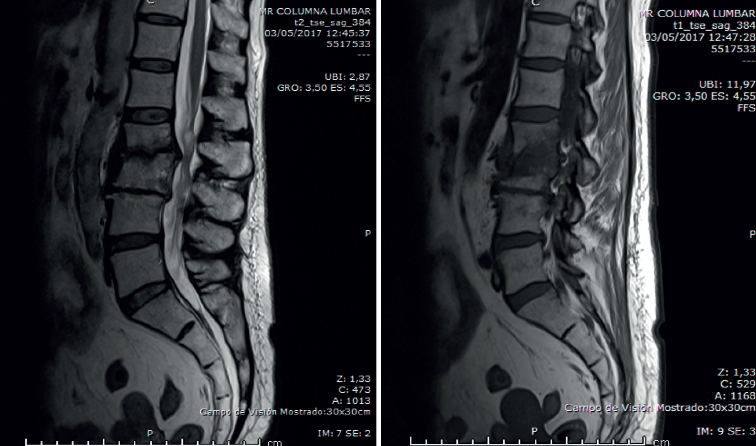

En la RM lumbar (Figura 4) se observaba desaparición de los abscesos preexistentes. Discopatía evolucionada.